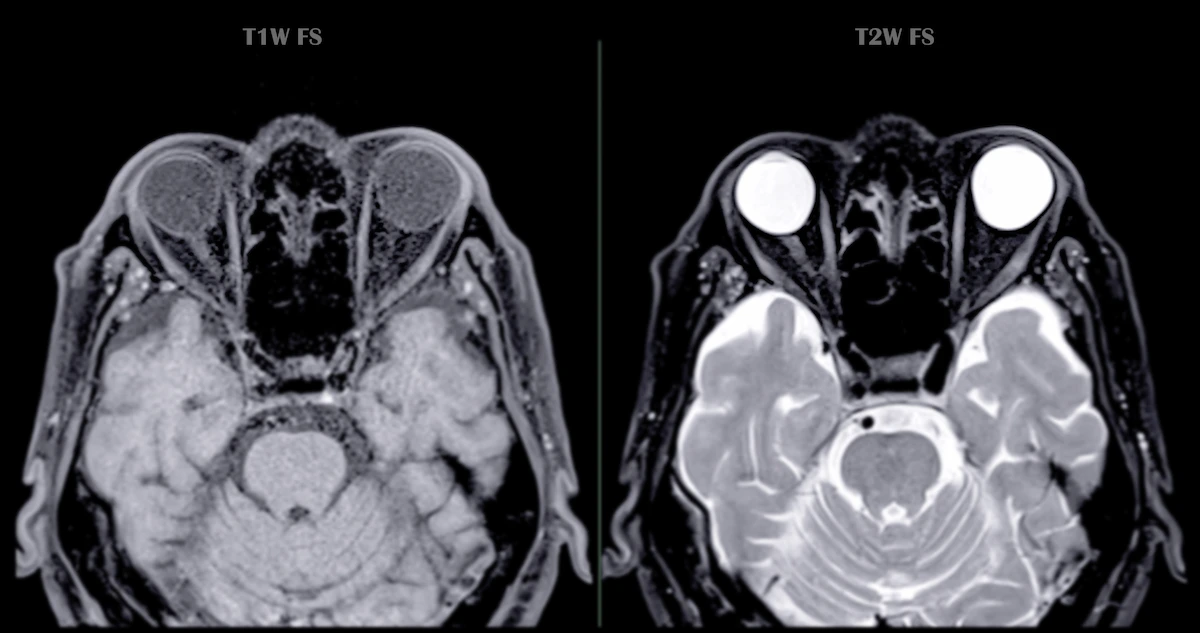

Magnetic Resonance Imaging (MRI) is a powerful diagnostic tool that uses magnetic fields and radio waves to create detailed images of the inside of your body. In some cases, a contrast agent is used to enhance the clarity of these images. If you’re in Miami and scheduled for an MRI, you might be wondering about the potential risks and side effects of MRI contrast.

Gadolinium is the most common contrast agent used in MRI scans. It’s a metallic element that, when injected into your bloodstream, can make certain tissues and structures show up more clearly on the MRI images.

- Enhance the visualization of blood vessels, tumors, infections, and inflammation.

- Help doctors distinguish between normal and abnormal tissue.

- Provide more detailed images for diagnosis and treatment planning.